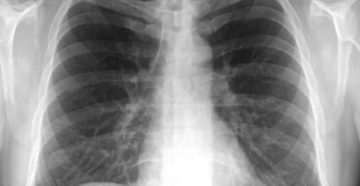

Рентгенография грудной клетки: показания к проведению диагностики Рентген грудной клетки — частая диагностическая процедура, которая…